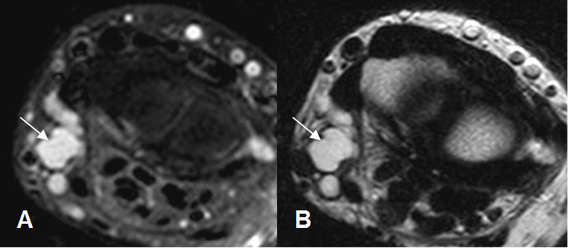

Fig 108 A. Ganglión quístico.

A: RM axial en T2 y B: RM axial en STIR. Lesión quística en la parte medial de la muñeca, que corresponde a ganglión quístico.